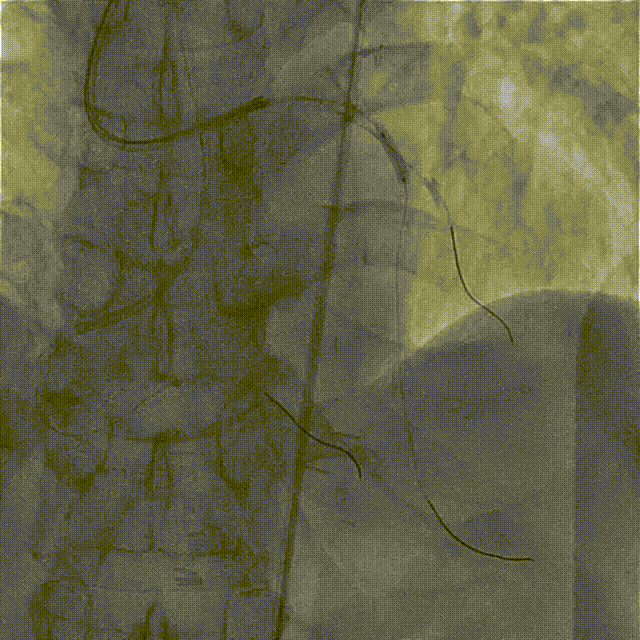

在HighTrack微导管的支撑下及逆向导丝的指引下,正向用Gaia First、Gaia Third、PILOT 200导丝反复尝试,均未能通过闭塞段进入血管真腔。

逆向重新送入一根SION Blue导丝反复尝试,最终进入正向指引导管内,推送逆向微导管至正向指引导管内,逆向送入RG3导丝至正向入口,正向沿RG3导丝推送微导管至LAD远段,撤出逆向导丝及微导管,交换一根SION Blue导丝至LAD远段。